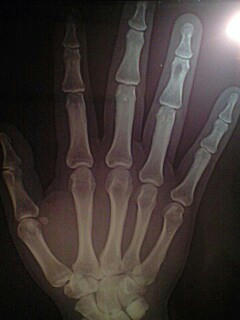

ところで昨日の受診でもDr.三上は、

右手第4指第1関節付近の画像の

黒く抜けて見える所を気にしていた。

手に大怪我をしたことなんて無いし、

グイグイ押されても何ともない。

「有るとしたら良性の腫瘍かな?」

大きくなってないし大丈夫だね、と、

そんなさらりと笑顔で云われても(汗